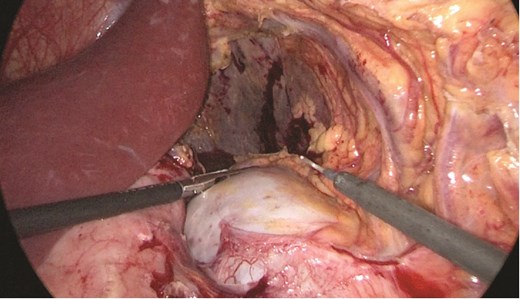

Multidisciplinary discussion was held to evaluate the most appropriate course of action for the patent condition, and the consensus was reached to pursue embolization as a first intervention. Embolization was performed by interventional radiology with no complications post-procedure, and the patient was optimized prior to her procedure. Patient was taken to the operating room in stable conditions. The spleen was enlarged around 20 cm. Inferiorly, the omentum and part of the transverse colon was attached to the spleen (Fig. 3), so we freed the omentum from the splenic tissue. The dissection continued until reaching short gastric vessels and entering the lesser sac (Fig. 4). Once the lesser sac was entered, the splenic vessels were identified (Figs 5 and 6), the splenic vein was hugely dilated with multiple collateral branching vessels at the hilum. Gaining posterior mobilization of the vein was challenging. The splenic artery was tortuous from the insertion around itself (Fig. 7). After complete mobilization of the fundus, we elected to divide each vessel starting with the splenic artery so we can achieve full mobilization of the vein (Fig. 9). After controlling the splenic artery, the splenic vein was dissected proximal to the splenic hilum (Fig. 8). It was hugely dilated and its wall is thickened secondary to AV fistula. It was difficult to achieve circumferential dissection, so we decided at that moment to convert to laparotomy to complete ligating the vein and to retrieve the specimen (Fig. 10a and b).

Splenic vein mobilized from the side. Clips seen on branches of the vein.